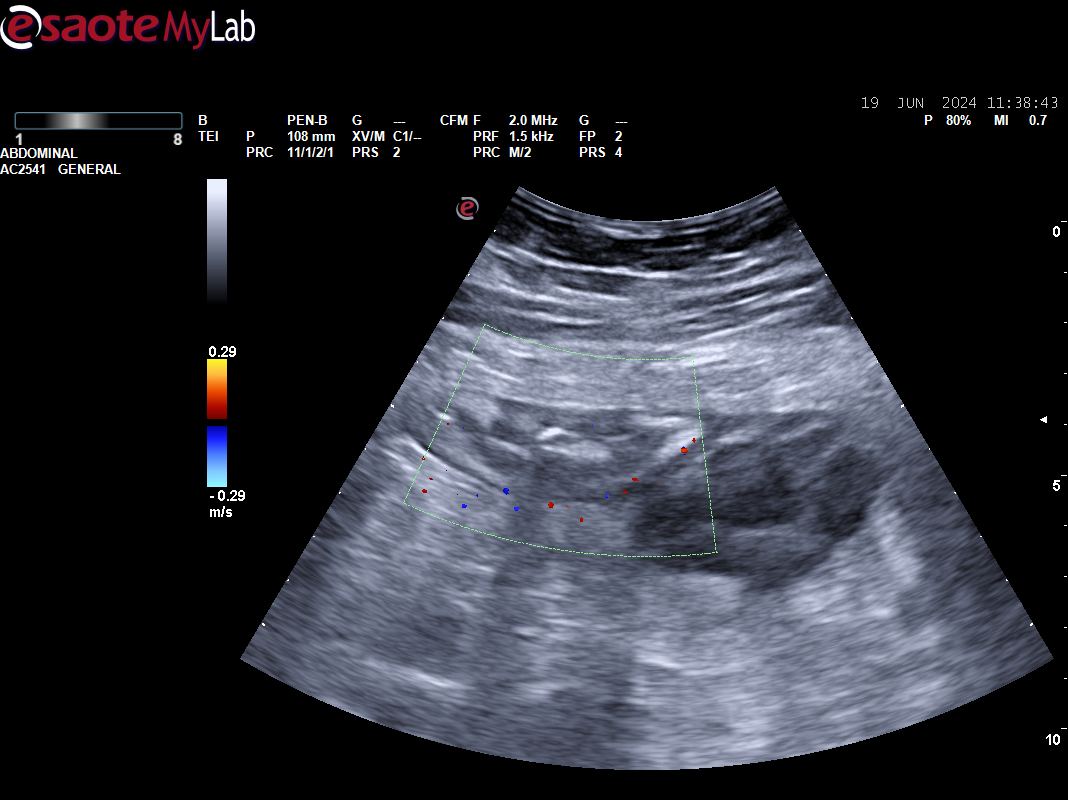

Paciente 2: vesícula distendida sin ecos en su interior, en línea media detectamos masa redondeada de 3-4 cm, Doppler positivo bajo proceso uncinado, dado dolor intenso no controlado se remite a urgencias e ingresa para estudio de posible masa pancreática.